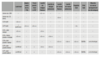

Lésions ligamentaires en fonction du testing du genou